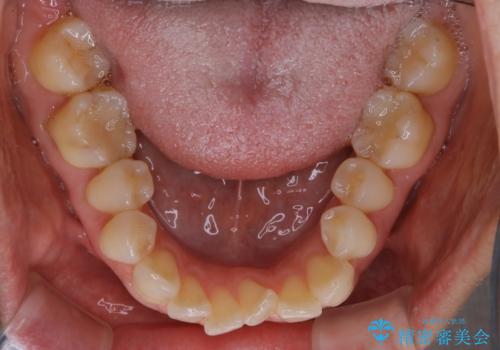

- 下の前歯のがたつきが気になるとの事でご相談にいらした患者様です。

元々はリンガルブラケットをご希望されていましたが、モニター制度を利用してインビザラインによる治療を行いました。

インビザラインFULLで奥歯の噛み合わせから改善させることで、上下の真ん中位置をしっかり合わせることが出来ました。

横顔のシルエットも改善させることができ、大変喜んでいただけました。